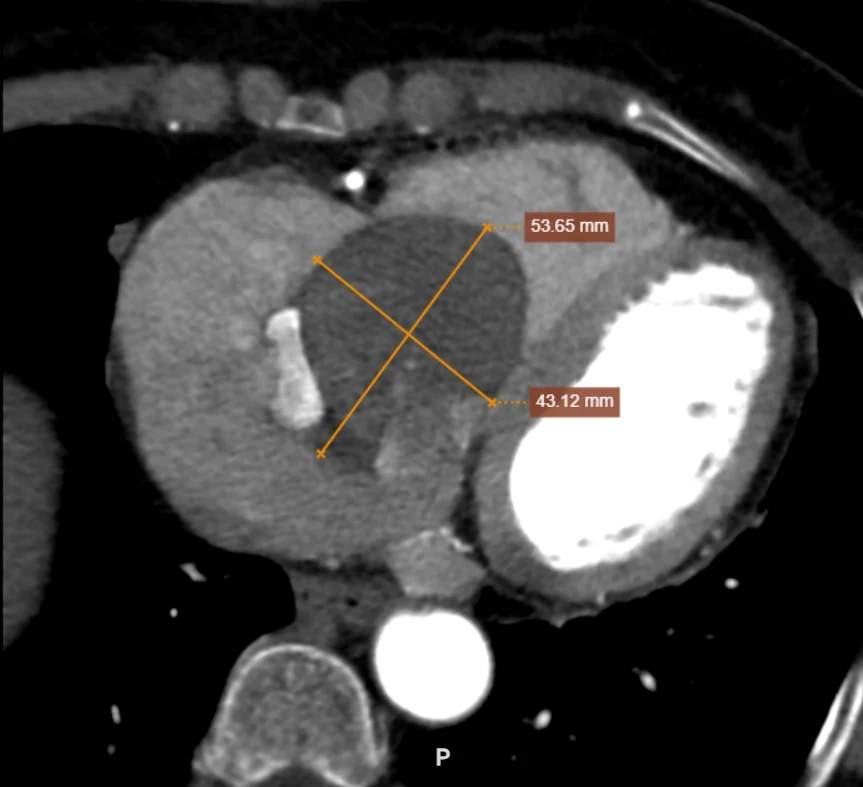

Tại Bệnh viện Đa khoa tỉnh, sau khi thực hiện các xét nghiệm, siêu âm tim và chụp cắt lớp vi tính (CT), các bác sĩ xác định người bệnh có một khối u nhầy khổng lồ kích thước 53x43mm nằm trong nhĩ phải, nguy cơ gây biến chứng nguy hiểm đến tính mạng.

Hình ảnh khối u khổng lồ qua phim chụp CT.